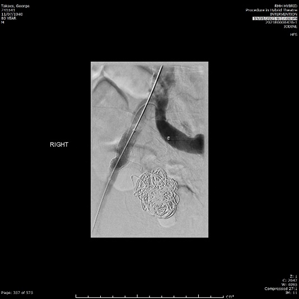

The endovascular procedure was performed with accesses via bilateral common femoral artery punctures. Through the left femoral puncture, an up-and-over approach was used to obtain Digital Subtracted Angiograms (DSA), which showed the saccular aneurysm beginning shortly after the right IIA origin, with no other feeding collaterals (Figure 3). Nester embolisation coils and thrombin were deployed and injected to fill the aneurysm. Post-intervention DSA showed very minimal filling of the aneurysm sac. A 13x5cm Viabahn covered stent graft was then inserted through the right femoral puncture and deployed over the common and external iliac artery, which covered the origin of the IIA. The groin punctures were closed with Angioseal Closure Devices.

Figure 3 Digital Subtracted Angiograms taken intraoperative pre- and post-intervention. (A) The saccular aneurysm is seen filling with contrast shortly after the origin of right internal iliac artery. (B) Successful exclusion of the aneurysm after using embolization coils and thrombin in the aneurysm, and deploying a covered stent graft across the common and external iliac artery.